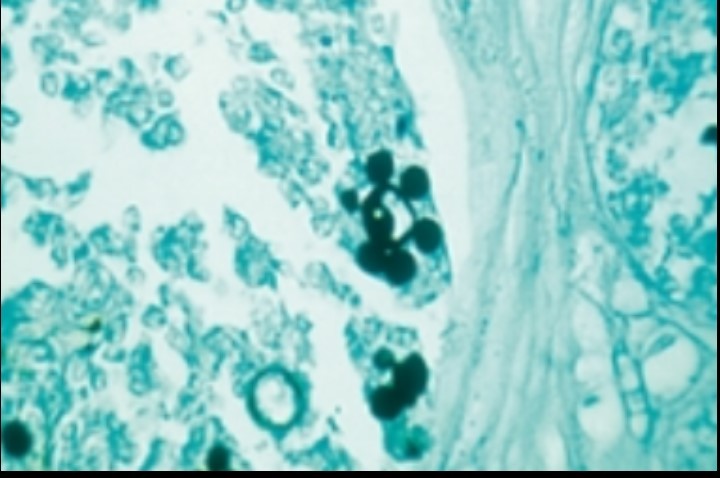

GMS, PAS on histopath - narrow-based budding w/ large capsule

crypto